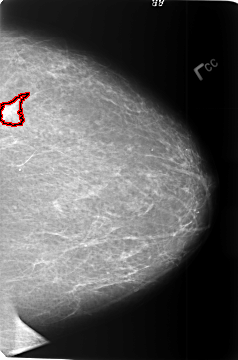

FILE: B_3391_1.LEFT_MLO.OVERLAY

TOTAL_ABNORMALITIES 1

ABNORMALITY 1

LESION_TYPE MASS SHAPE IRREGULAR-ARCHITECTURAL_DISTORTION MARGINS SPICULATED

ASSESSMENT 4

SUBTLETY 3

PATHOLOGY MALIGNANT

TOTAL_OUTLINES 1

BOUNDARY